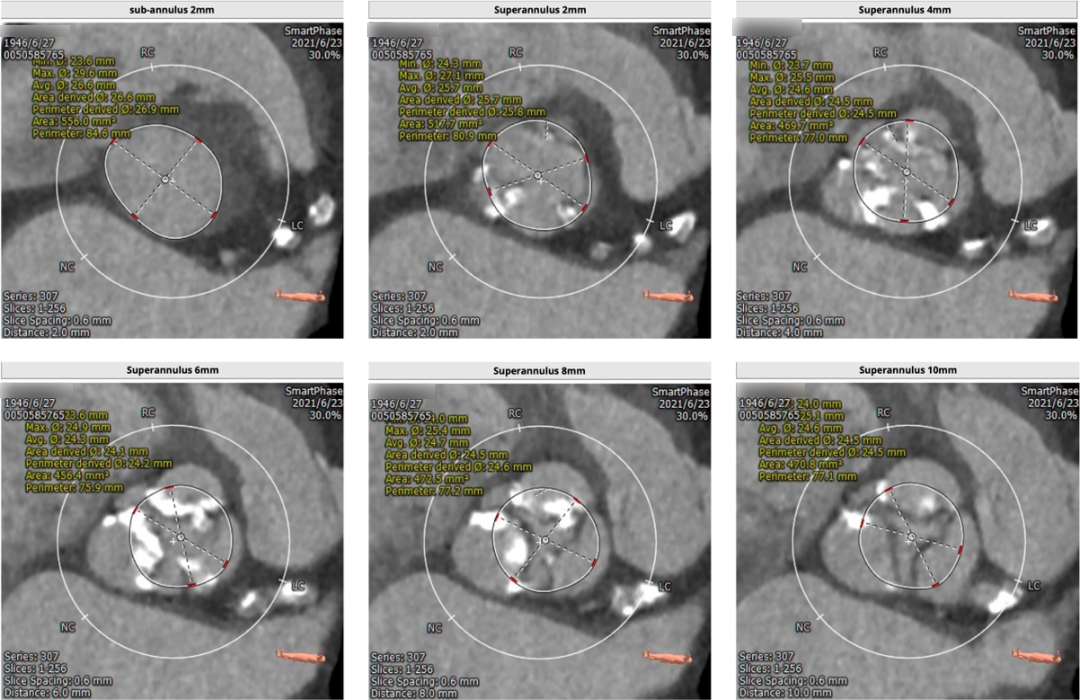

术前CT

CT提示为该患者三叶瓣,右无轻度融合,冠脉开口高度尚可,窦部空间可,髂总动脉近环形钙化,内径可,计划予以23mm球囊扩张,植入Venus A 26瓣膜。